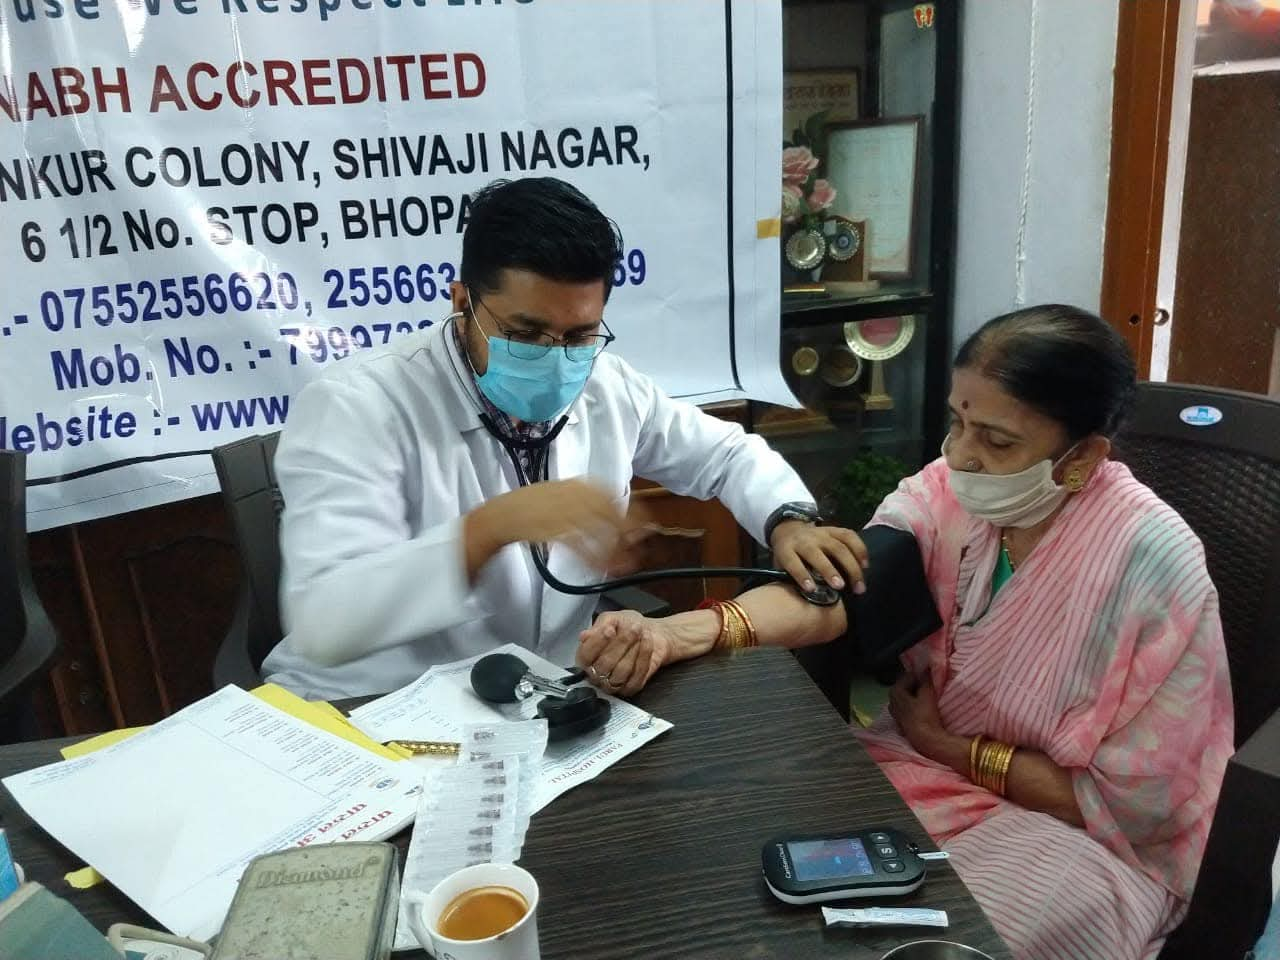

Community Health Outreach & Recognition

A meaningful blend of senior citizen health interaction, clinical consultation, medical outreach, recognition moments and academic participation.

Elderly Care

Personalized Doctor Interaction

Recognition Moment

Community Appreciation • Trophy • Group Felicitation

Event Snapshot

Senior citizen wellness, medical screening & public care activity

These images highlight a community-focused healthcare activity where senior citizens were engaged through consultation, health screening, direct doctor interaction and social recognition.

Senior Citizen Forum

Hospital Branding Visible

Parul Hospital

Because We Respect Life • NABH Accredited

Why It Matters

Care that reaches the community

This outreach reflects preventive health support, trust-building and compassionate care for elderly members.

Community Camps

Health interaction in real social settings.

Senior Wellness

Focused care, checkups and personal attention.

Medical Presence

Clinical credibility backed by academic involvement.